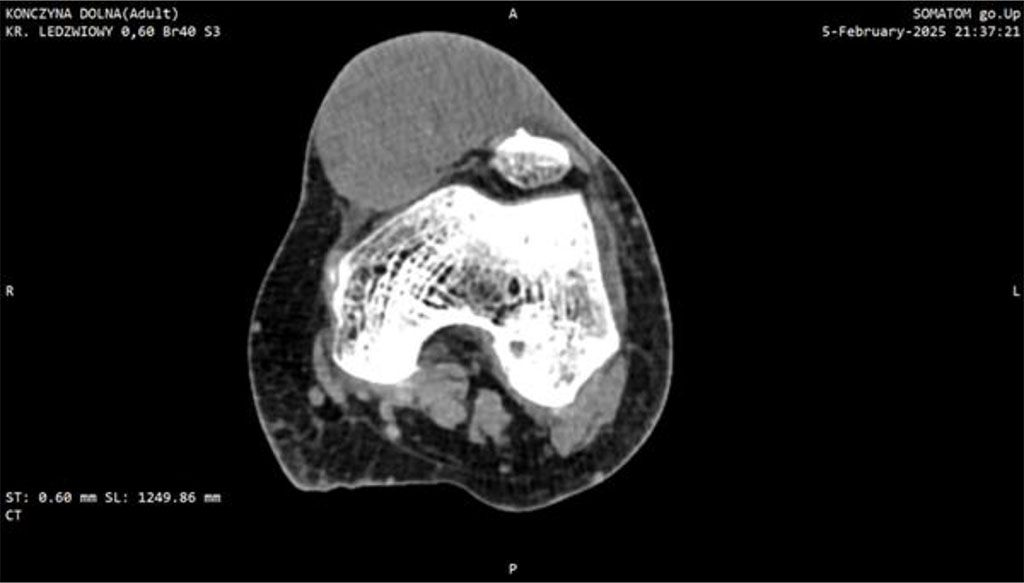

Within one month post-surgery, the lesion expanded dramatically to ~7 cm, became markedly erythematous, cyanosed, and showed areas of necrosis. This raised a suspicion of a malignant tumor which led to extended diagnostic. CT imaging identified a soft-tissue mass with dense fluid components (73 × 40 × 70 mm), without patellar destruction or intra-articular effusion (Fig 1, 2).

Figure 2: CT scan of the knee joint with Myxofibrosarcoma (MFS). Axial plane.